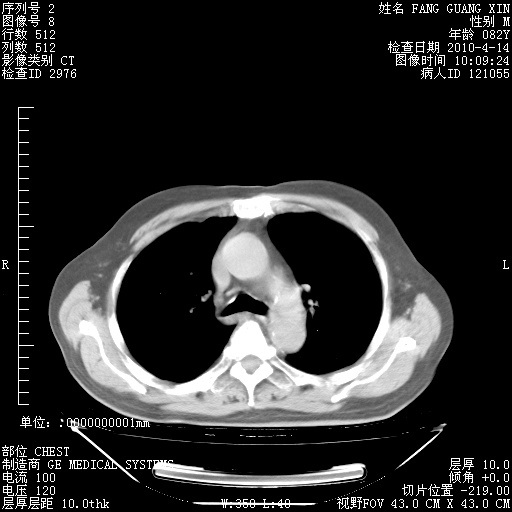

4月14日肺部CT

楼主| 发表于 2010-4-28 16:51 | 显示全部楼层

楼主| 发表于 2010-4-28 16:53 | 显示全部楼层

楼主| 发表于 2010-4-28 16:59 | 显示全部楼层

肺部CT平扫未见异常。